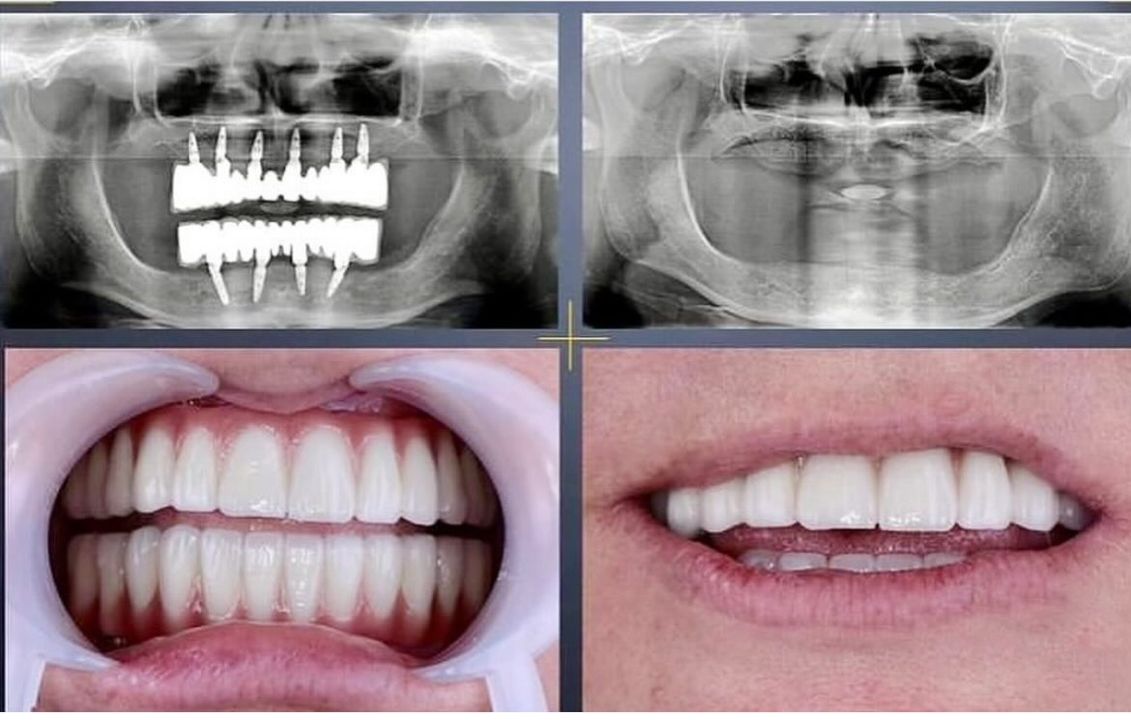

İmplant tedavisi

İmplant Tedavisi ile Kalıcı ve Güvenli Çözüm

İmplant tedavisi, eksik dişlerin yerine çene kemiğine yerleştirilen titanyum vidalar sayesinde doğal diş fonksiyonunu yeniden kazandıran modern ve kalıcı bir yöntemdir. Kemikle biyolojik uyum sağlayan implantlar, üzerine yerleştirilen protezlerle birlikte hem estetik hem de fonksiyonel açıdan güçlü bir sonuç sunar.

Eksik dişler zamanla kemik kaybına ve çevre dişlerde bozulmaya neden olabilir. İmplant tedavisi, kemik yapısını destekleyerek bu sürecin önüne geçmeye yardımcı olur. Sağlam bir temel, sağlıklı ve özgüvenli bir gülüş demektir.